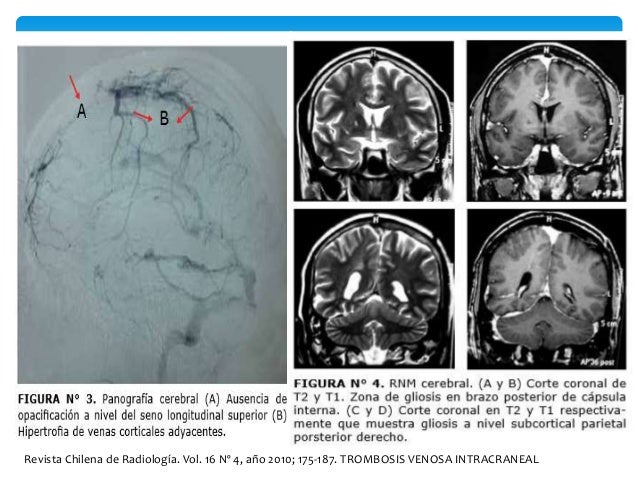

20. 20. Revista Chilena de Radiología. Vol. 16 Nº 4, año 2010; 175-187. TROMBOSIS VENOSA INTRACRANEAL

21. 21. Revista Chilena de Radiología. Vol. 16 Nº 4, año 2010; 175-187. TROMBOSIS VENOSA INTRACRANEAL